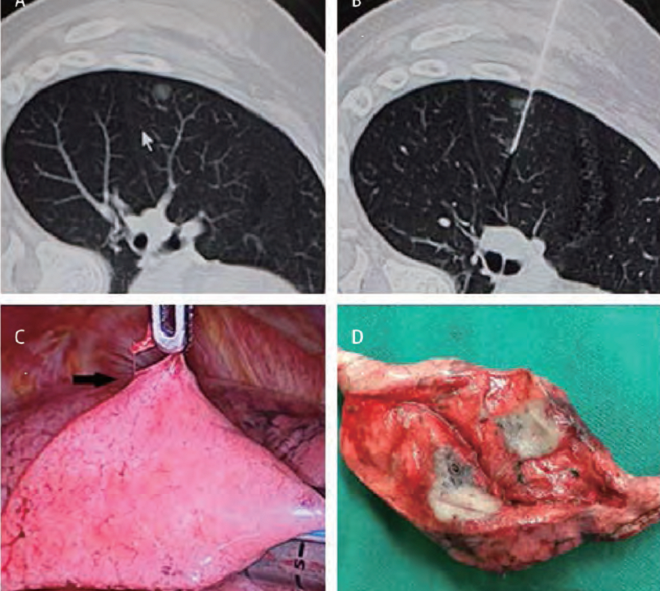

肺部結(jié)節(jié)是指肺部出現(xiàn)的圓形或不規(guī)則形狀的異常組織增生,通常通過(guò)醫(yī)學(xué)影像技術(shù)如X光、CT掃描等檢查發(fā)現(xiàn),肺部結(jié)節(jié)可能是良性的,也可能是惡性的,其形成原因多種多樣,包括感染、炎癥、良性腫瘤和肺癌等。